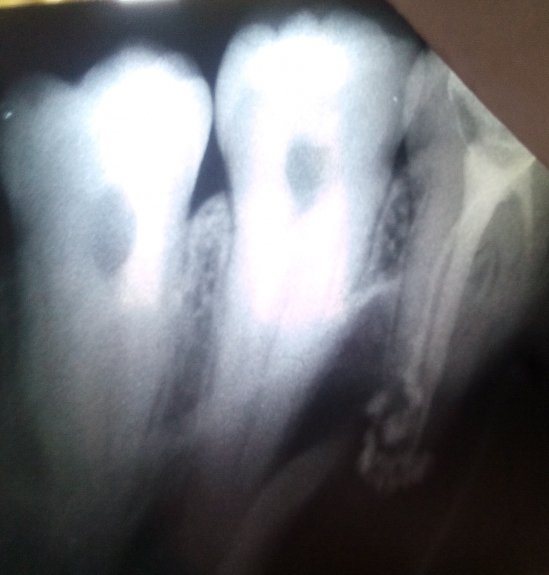

Плохо запломбированы каналы